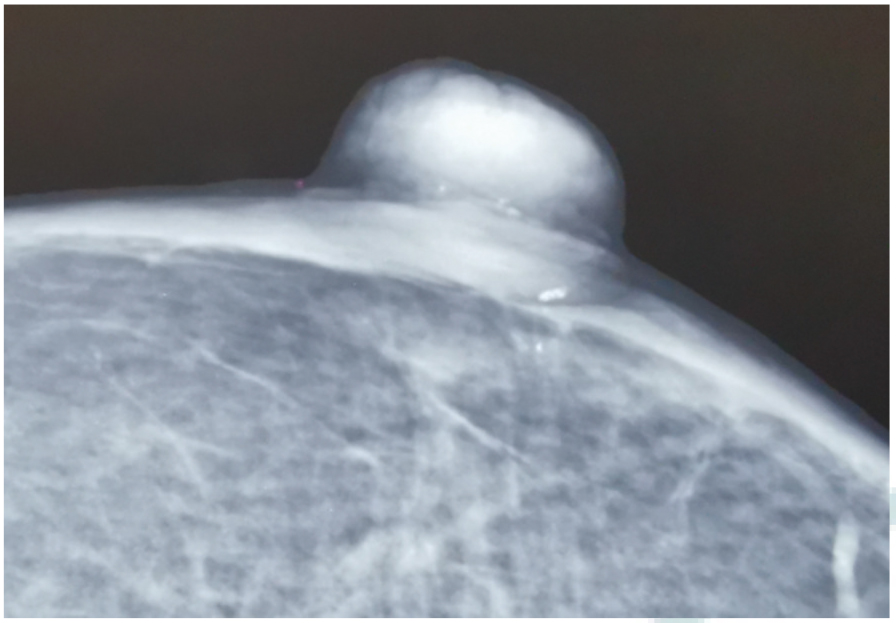

小汗腺汗孔癌(EPC)又称外泌汗腺汗孔癌,是一种少见的皮肤附属器恶性肿瘤,通常起源于小汗腺的导管,好发于头颈部和四肢皮肤,发生在乳头部位的较为罕见。现报道1例左乳头EPC患者的诊疗过程,复习相关文献并讨论,以期为临床提供诊疗思路。